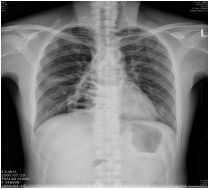

8.右胸痛 3 個月